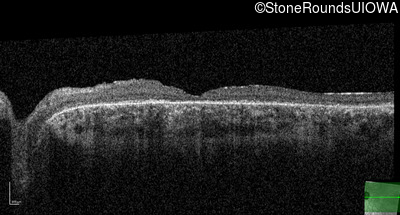

Optical Coherence Tomography - Right - 20/100 -1 sc

Exemplar / OCT Stack

OCT Stack